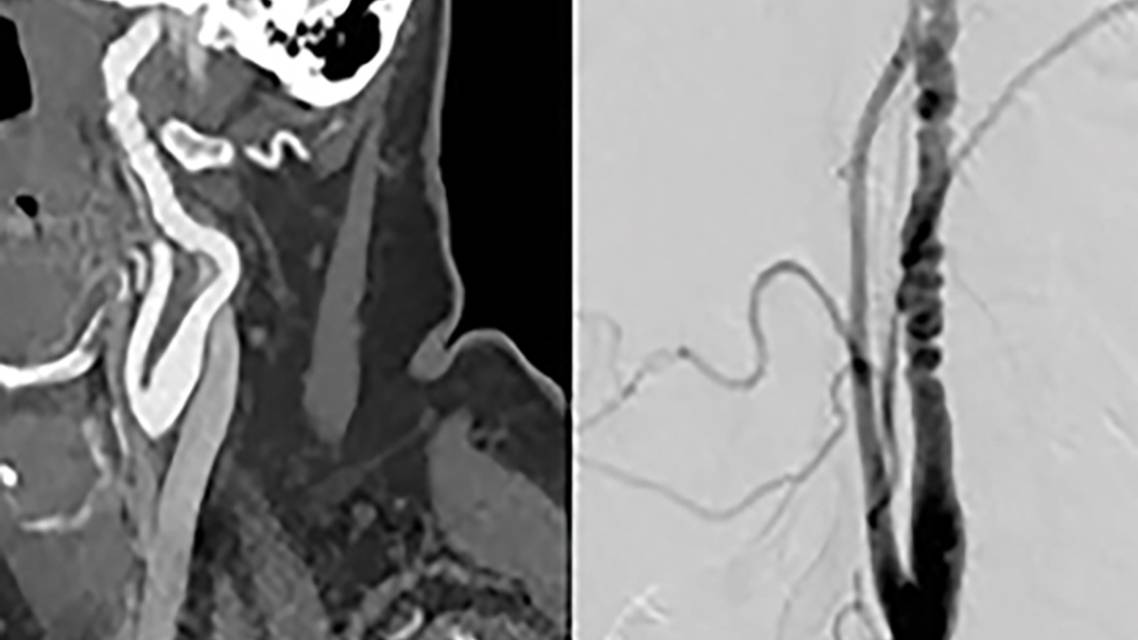

In this issue, several internationally recognized experts provide updates about some of the less common causes of stroke. We begin with Mitchell S. V. Elkind discussing the broader category of Atrial Cardiomyopathies and Stroke, an expanded understanding of atrial fibrillation. Next, Ilana E. Green, Andrew M. Southerland, and Bradford B. Worrall share an update on Fibromuscular Dysplasia and Stroke, including the presentation and management of the condition. The importance of Infectious Causes of Stroke, and how to recognize and treat bacterial, viral, and fungal infections is ably covered by Jennifer E. Fugate. Next, we cover a genetically driven cause of stroke: Moyamoya Disease by Alaa Montaser and Edward Smith. We then turn to immune-related strokes with my contribution on Takayasu Disease and finish with Susac Syndrome, now shown to be an autoimmune disease, by Ilka Kleffner, Catharina C. Gross, Marius Ringlestein, Jörg Rehrmann, MD Markus Kraemer, and Jan Dörr.